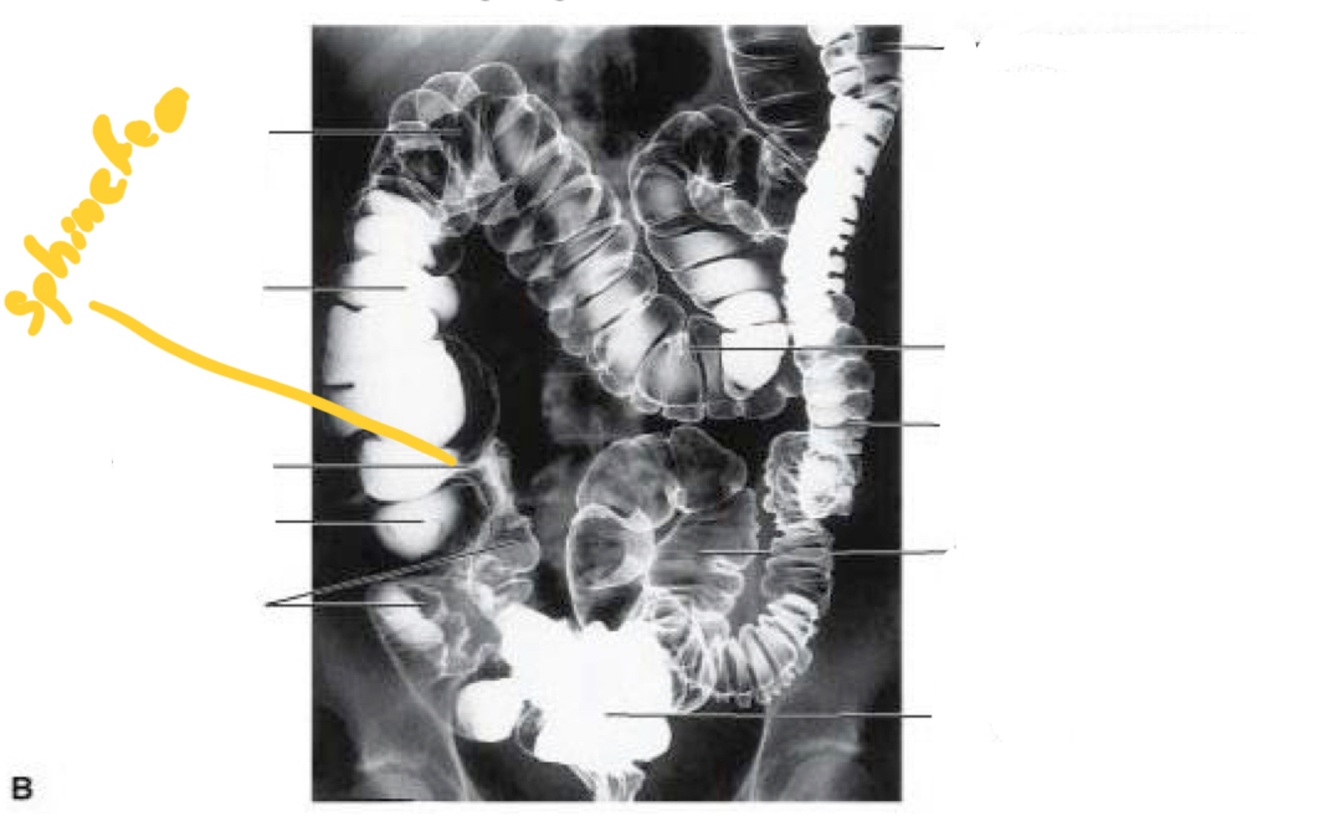

Barium enema enables…

… imaging to access function

Colon divided into:

• Ascending

• Transverse

• Descending

• Sigmoid

• Ascending • Transverse • Descending • Sigmoid

• Ascending and

descending colon

are retroperitoneal

• Transverse and

sigmoid colon are

intraperitoneal